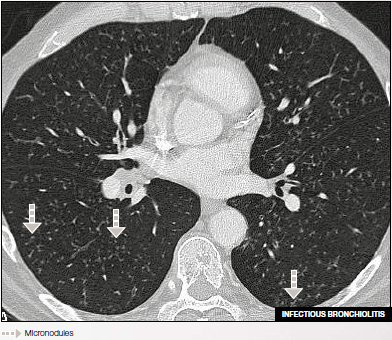

• Infectious bronchiolitis

Bilateral micronodules sparing the subpleural lung.